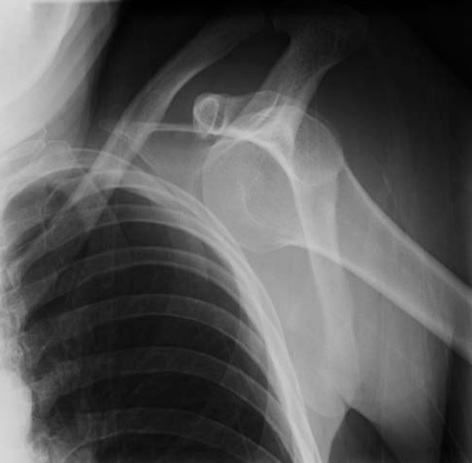

2. What is this diagnosis..?

a. The small majority of shoulder dislocations are anterior, and the large majority of anterior dislocations are subcoracoid, as demonstrated in this AP view.

b. The large majority of shoulder dislocations are posterior, and the samall of anterior dislocations are subcoracoid, as demonstrated in this AP view.

c. The large majority of shoulder subluxaxion are anterior, and the large majority of anterior dislocations are subcoracoid, as demonstrated in this AP view.

d. The large majority of shoulder dislocations are anterior, and the large majority of anterior dislocations are subcoracoid, as demonstrated in this AP view.